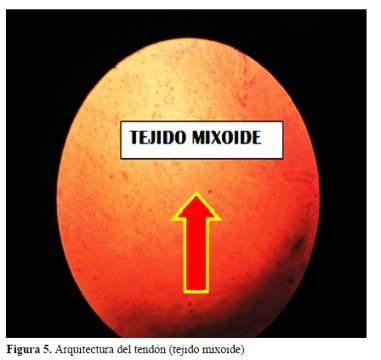

Al explorar los miembros inferiores, llamó poderosamente la atención el volumen de las regiones aquilianas aumentado y en forma de conos invertidos por la presencia de xantomas (figura 3 (A y B)). Se efectuó biopsia de la región aquiliana que mostró el tendón alterado con un área de proliferación histiocitaria en relación a lesión xantomatosa (figura 4), y la arquitectura del tendón reemplazada por tejido mixoide (figura 5).

Los xantomas tendinosos aquilianos, biopsiados mostraron la naturaleza de la enfermedad, al igual que la presencia del arco senil tempranamente aparecidos, antes de los 30 años, las cataratas, la presencia de xantoma en el cuerno ventricular derecho por la especialidad y la osteoporosis estarían indicando un estado avanzado de la enfermedad por XCT. El estudio con resonancia magnética del cerebro (RM), puso en evidencia los cambios morfológicos del tejido cerebral, asi como , la penetrancia del colagenol en estructuras específicas empleando la incidencia del FLAIR.

La presencia de los hallazgos oftalmológicos y las características morfológicas de las regiones aquilianas permitieron sospechar clínicamente de la la presencia de xantomatosis que se confirmó mediante los resultados histopatológicos de la biopsia efectuada. Los resultados de la exploración neurológica mostraron un estado demencial severo asociado a definidas alteraciones de la función cerebelosa.